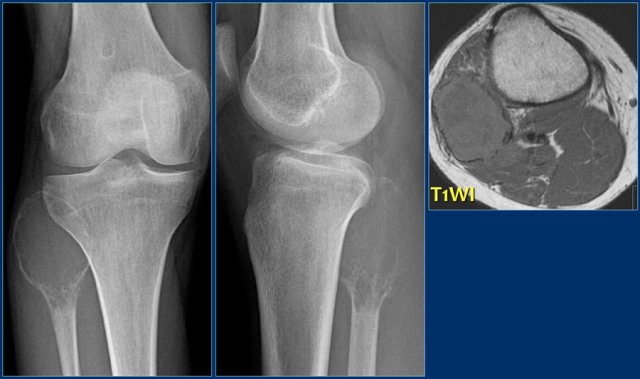

Giant cell tumor

key facts:

• Presents as an eccentric lytic lesion with a geographic pattern of bone destruction, but can also have a more aggressive appearance with ill-defined borders.

• By far most giant cell tumors are seen around the knee. GCT is located in the epiphysis with or without extension to metaphysis and frequently abuts the articular surface.

• Most common bone tumor in adults aged 25 - 40 y.

GCT in distal femur GCT in distal femur

Giant cell tumor (2)

On the left a giant cell tumor presenting as an eccentric lytic lesion in the medial epi- and metaphysis of the distal femur.

There is a small transitional zone resulting in well-defined borders.

On the left more examples of GCT around the knee.

Notice that most of these lesions are well-defined and located in the epiphysis and extend into the metaphysis.

Some extend onto the articular surface (yellow arrow and small red arrows).

The lesion on the upper right has an ill-defined border with a broad zone of transition (blue arrow).